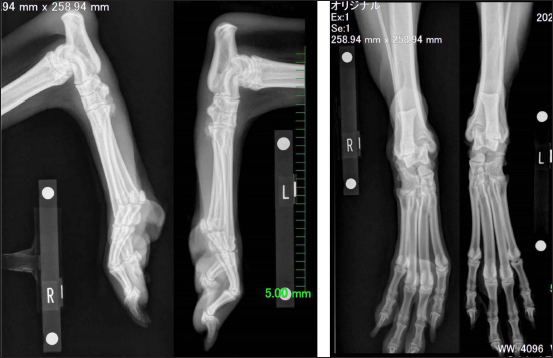

On examination at our hospital, a Monroe walk was observed, with a Grade I lameness score of the right hind limb. On orthopedic examination, swelling, and warmth of the right tarsal joint were observed, as well as crepitus and pain during extension and flexion. Lateral mobility of the Achilles tendon attachment was observed when the affected limb was flexed. Radiographic examination showed increased soft tissue opacity around the caudal aspect of the right calcaneus (Fig. 1). Ultrasonography revealed a hyperechoic structure and fluid retention around the right Achilles tendon (Fig. 2). Based on these observations, we diagnosed lateral luxation of the SDF. Presurgical medication consisted of continuous infusion of butorphanol (0.2 mg/kg intravenously), medetomidine (2 μg/kg intravenously), and lidocaine (1 mg/kg intravenously). In addition, robenacoxib (2 mg/kg) was administered subcutaneously for analgesia. Ropivacaine (3 mg/kg) was administered for the sciatic nerve block. Intravenous propofol (6 mg/kg) was administered for the induction of anesthesia, and anesthesia was maintained with oxygen-sevoflurane. The overall general anesthesia time was 91 minutes, and the operation time was 68 minutes. The collected joint fluid was serous, and postoperative Diff-Quick staining showed a large number of macrophages, suggesting chronic inflammation (Fig. 3A). Medial capsulorrhaphy of the tarsal joint, arthrodesis, in which the shallow digital flexor tendon was sutured with 2–0 polydioxanone, and fixation with a 1.5-mm Kirschner wire were performed (Figs. 3B and 4A). Postoperatively, the tarsal joint was stretched to prevent tension on the tendon. A cast made of Castrolite Alpha® (ALCARE Corporation, Tokyo, Japan) was applied without the cranial aspect; and the Robert Jones bandage technique was used for stabilization (Fig. 4B). Postoperative medication consisted of intravenous cefazolin (20 mg/kg), subcutaneous sodium carbazochrome sulfonate (0.5 mg/kg), and tranexamic acid (10 mg/kg) twice daily for 3 days. Cefazolin (20 mg/kg twice daily) was also administered until suture removal. The Robert Jones bandage was removed on postoperative day 28. Finally, we removed the pin on postoperative day 88 under general anesthesia using the same methods as previously described. The patient walked well without pain and lameness 12 days after the removal of the pin.

Fig. 1. Radiographs showing increased soft tissue opacity around the caudal aspect of the right calcaneus.